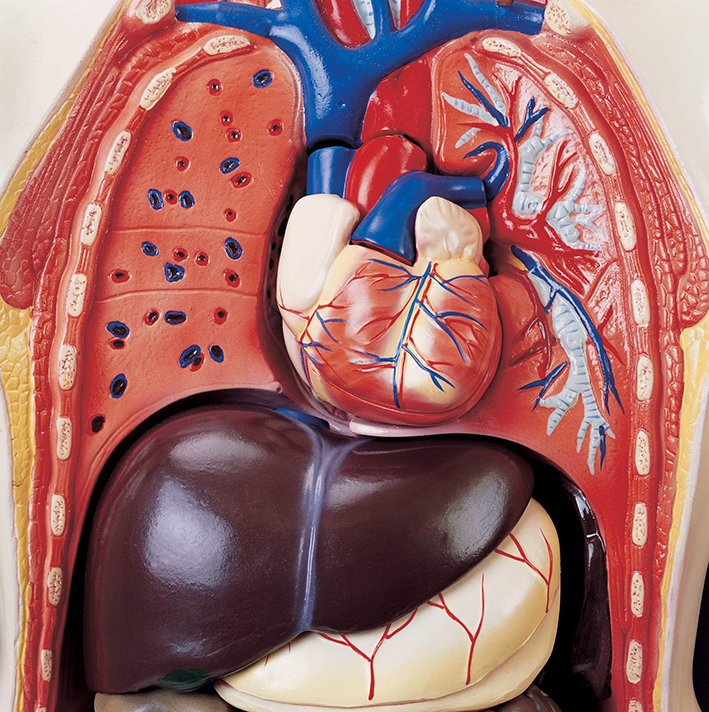

عکس داخل شکم انسان. در این همان طور که مشخص است شکم حالت بیضی شکل پیداکرده و این بیضی که کناره های شکم کشیده شده است. تعداد سلول های بدن انسان حدود ۳۷ ۲ تریلیون تخمین زده شده اند. Abdomen که در زبان عامه به غلط به آن دل نیز می گویند در آناتومی به قسمتی از تنه گفته می شود که مابین دیافراگم از بالا و سطح فوقانی لگن خاصره از پایین قرار دارد. ربات دیدنی ربات انساننمای چینی به صورت یک دختر جوان ساخته شده و جیا جیا نامگذاری شده است این ربات طوری برنامهریزی شده که میتواند صحبت کند و احساسات خود را از طریق تغییرات در چهره حالات.